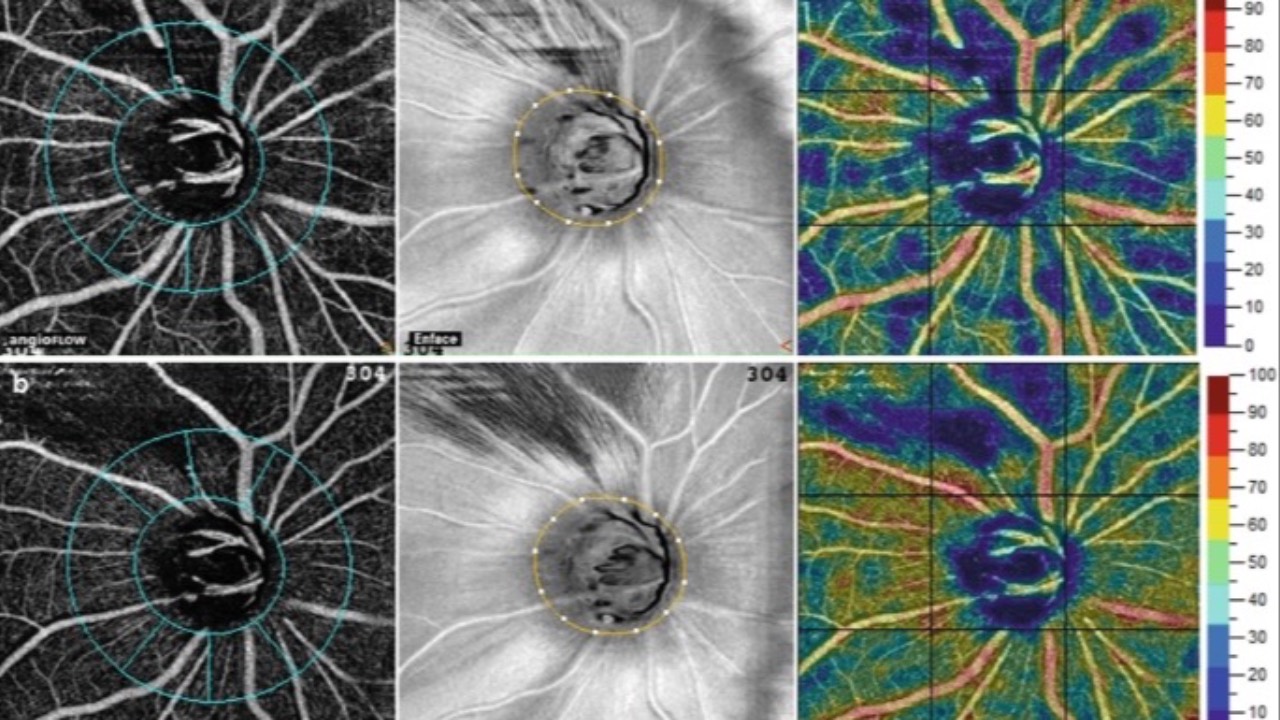

Nitric Oxide, OCTA & Glaucoma

NO3 via Vyzulta (latanoprostene bunod) may just matter.

A recent investigation was published regarding the impact of latanoprostene bunod on optical coherence tomography angiography (OCT-A) parameters in newly diagnosed open-angle glaucoma patients.

Changes in both vessel density and intraocular...